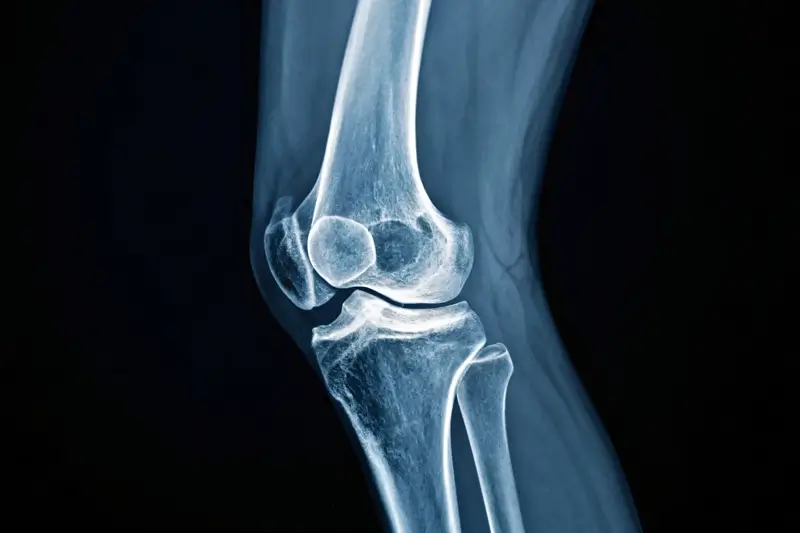

Bildgebende Untersuchung zur Beurteilung von Knochen, Gelenken und Fehlstellungen.